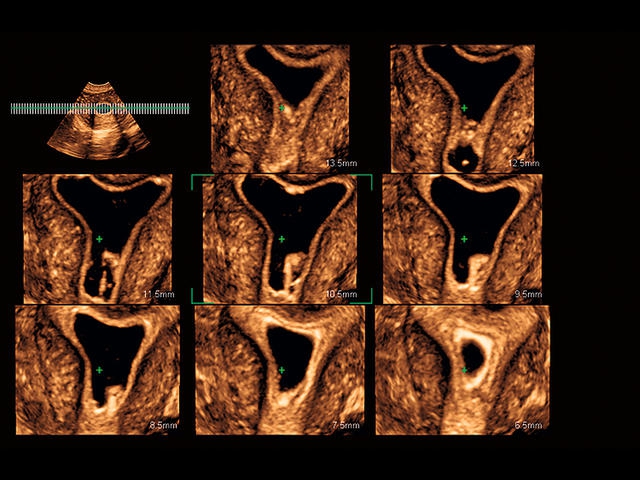

Обновленная версия легендарного УЗ-сканера. Стационарный аппарат экспертного класса Aplio 500 Toshiba NEW, визуализирует анатомические структуры в высоком разрешении. Модель позволяет выявить микрокальцификаты, новообразования, нарушения в работе сердца, сосудов и мышц. Присутствует функция виртуальной эндоскопии, 4D-сканирования, эластометрии тканей, УЗИ с контрастированием. За повышение качества изображения отвечают технологии ApliPure и Superb Microvascular Imaging. Первая задействует возможности пространственного и частотного кодирования, формирует цельный визуальный ряд с сохранением клинических маркеров. Вторая улучшает отображение микрососудистого русла, используя доплеровский эффект. Модель оснащена 21-дюймовым монитором, имеет 4 активных порта. Возможно подключение педиатрических, интраоперационных, лапароскопических и чреспищеводных датчиков.

• Fly Thru. Виртуальная эндосонография обеспечивает построение трехмерной модели полостей, протоков и сосудов в рельном времени, облегчает организацию инвазивных процедур и динамических исследований. Посредством Fly Thru можно установить шунты и стенты, проводить точные оперативные вмешательства.